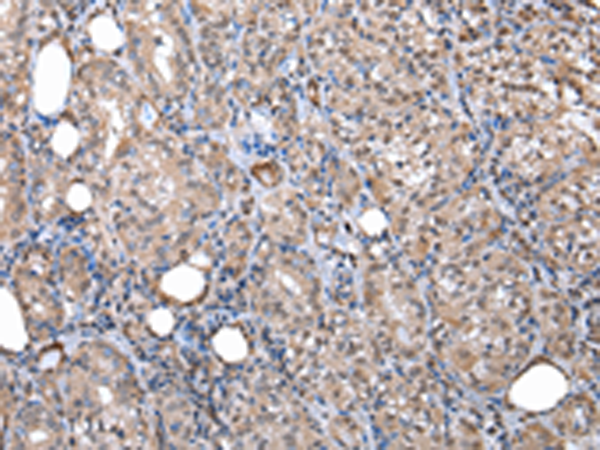

分类: 科研抗体货号: P01946别名: EGP1; GP50; M1S1; EGP-1; TROP2; GA7331; GA733-1应用: IHC反应种属: Human, Mouse, Rat